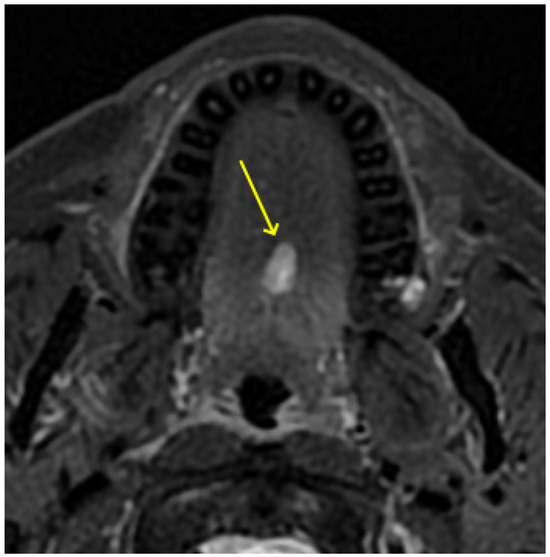

2. Detailed Case Description